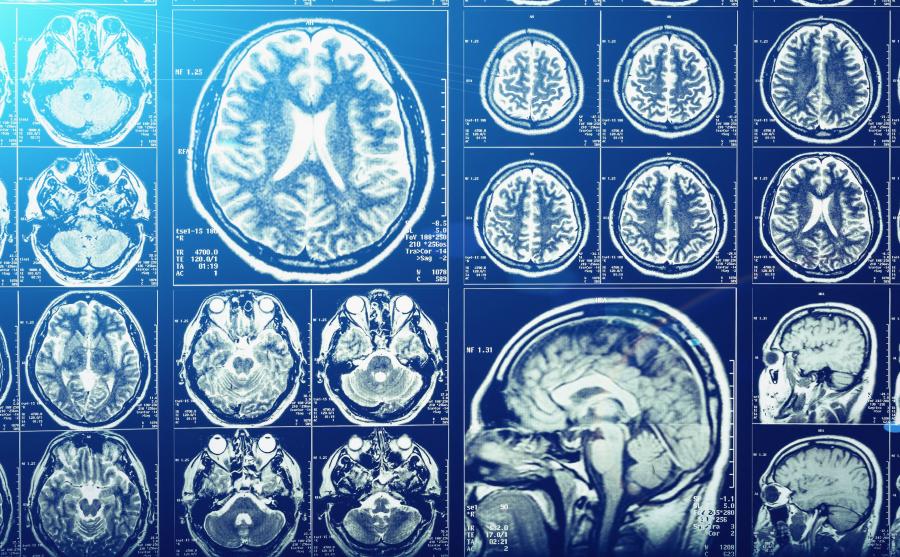

Ochrona mózgu przed urazami - dokument [*.doc] OCHRONA MÓZGU PRZED URAZAMI Anatomia Czaszka Opony – 3 błony tkanki łacznej PMR Zbiorniki płynowe Cały aparat.

Funkcje czaszki Podstawową funkcją czaszki jest ochrona mózgu i narządów wewnętrznych przed urazami mechanicznymi. Dodatkowo kości twarzoczaszki chronią.

1. Mózgowie Na mózgowie składa się: => półkule mózgowe => móżdżek => pień mózgu Położenie: Mózgowie znajduje się wewnątrz czaszki , jest otoczona oponami mózgowymi.

Mózgowie zbudowane jest z dwóch półkul mózgowych, móżdżku oraz pnia mózgu. Wraz z rdzeniem kręgowym tworzy układ nerwowy ośrodkowy (centralny układ nerwowy)..

Czaszka – budowa, funkcje i złamania czaszki. Czaszka człowieka to charakterystyczna część układu szkieletowego, która odpowiada za ochronę mózgu, narządów.